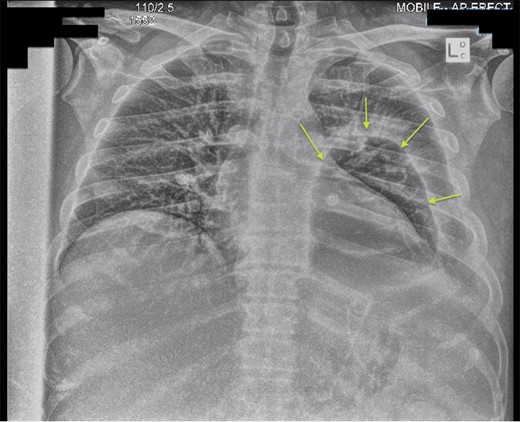

Chest X-ray in ICU following drainage showed what was thought to be Pneumomediastinum (Figs 1 and 2), and given this concern he was referred to the Cardiothoracic service. Subsequent CT suggested a large loculated hydro-pneumothorax, which in retrospect represented the drained Pseudocyst communicating through the diaphragm (Figs 3 and 4).

Area of communication between the drained Pseudocyst and the Left Pleura. Space noted with arrow.